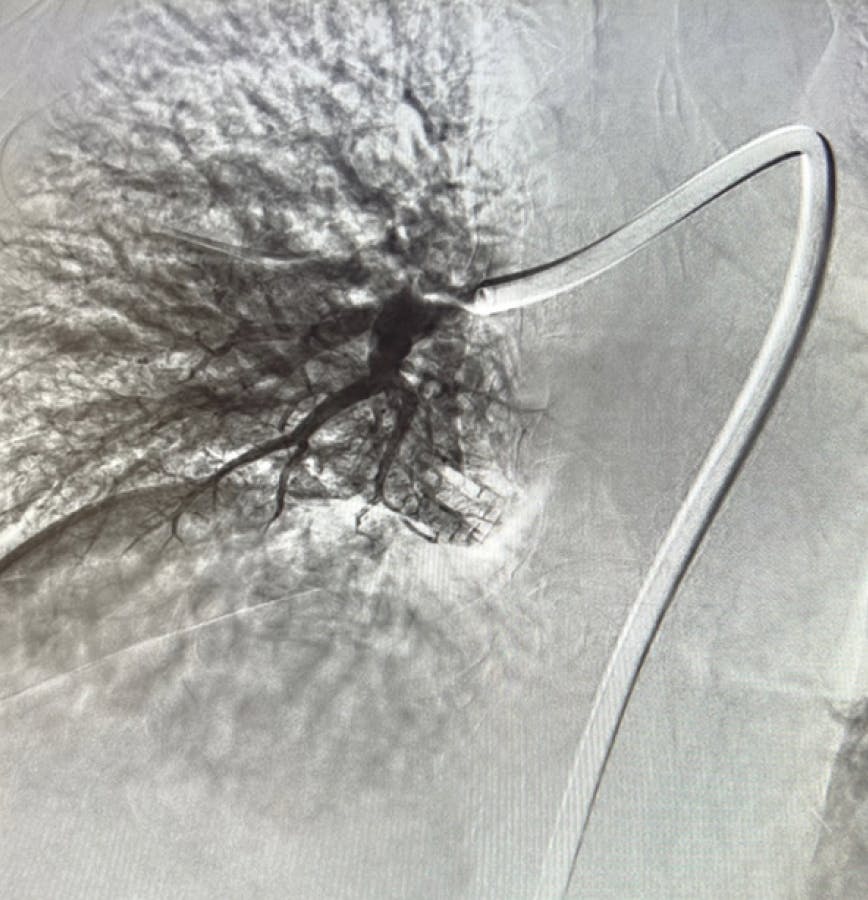

Figure 1. Right lobe initial angiogram.

Figure 2. Left lobe initial angiogram.

Figure 1. Right initial angiogram.

Figure 2. Left initial angiogram.